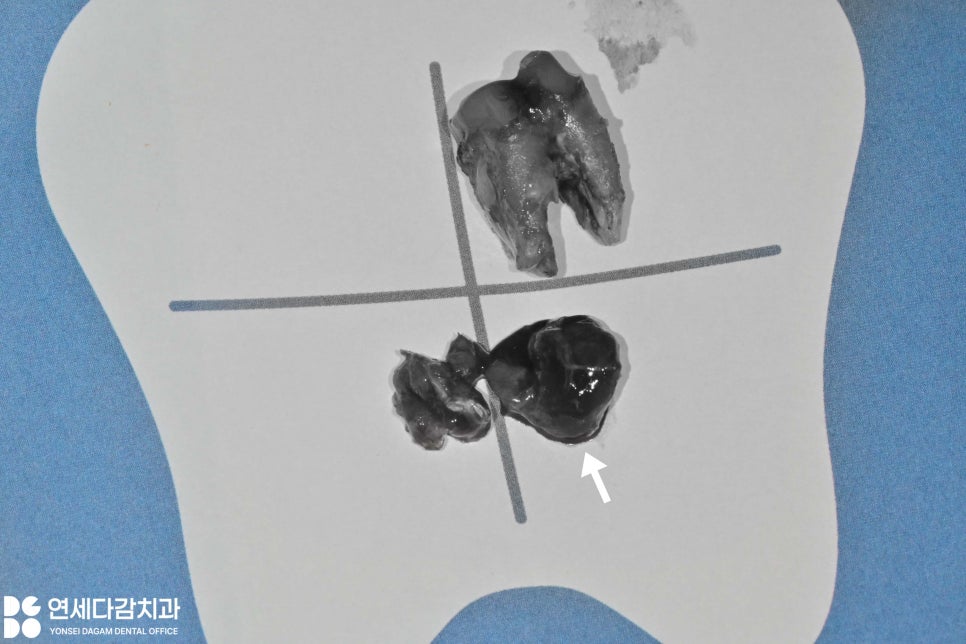

발치를 진행할 때는

치아만 제거하는 것이 아니라

치근단에 형성된 염증 조직을

깨끗하게 적출하는 것이

중요합니다.

치근단낭이 깔끔하게 적출된 모습

이를 뺀 발치와 부위를

깨끗하게 긁어내는 소파(curettage)

과정이 꼼꼼하게 진행되어야

발치 후 회복이 원활하게 진행되고

재발을 방지할 수 있습니다.

술 후에는 치근단 촬영을 통해

꼼꼼하게 확인한 후

소독하여 마무리하게 됩니다.